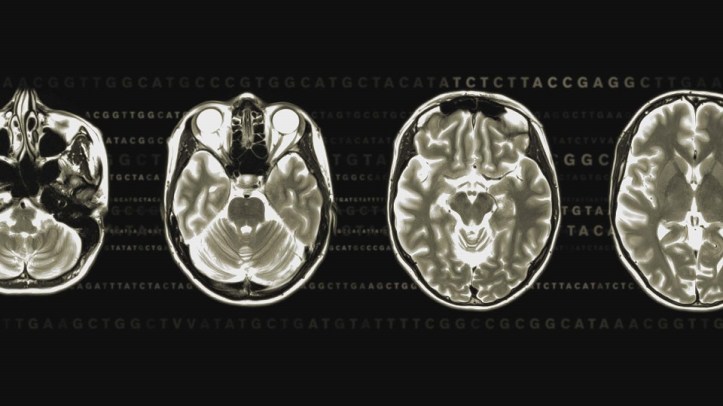

Neurotieteistä tohtoriksi väitellyt tiedetoimittaja järkyttyy kun hän menee unelmatreffeille, joiden jälkeen mies sanookin, ettei voi sietää häntä. Tanskalainen Lone Frank haluaa muuttaa persoonaansa, joka tuntuu olevan törmäyskurssilla muun maailman kanssa. Pernille Rose Grønkjærin ohjaamassa dokumentissa Lone selvittää tutkijoiden avulla mistä persoonamme muodostuu ja voiko sitä muuttaa.